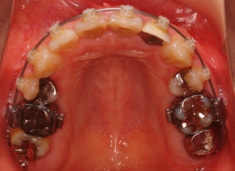

治療開始時